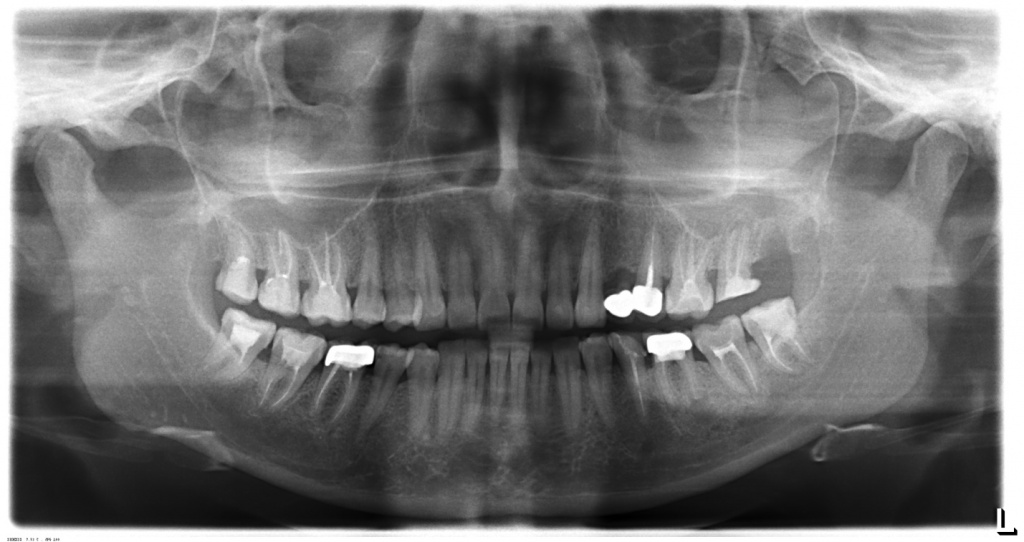

Ортопантомограммы пациентов до и сразу после имплантации. В 1-ом случае имплантат в позиции 36 и 27 , а на 2-ом снимке часть имплантатов установлены немедленно после удаления зубов.

CASE №1

Планируется установка имплантата в позиции 17.

CASE № 2

На нижней челюсти планируется установка условно-съемного протеза на балке. После протезирования на нижней челюсти планируется решение вопроса о протезировании на верхней челюсти (по настоянию пациента сроки раздвинуты).